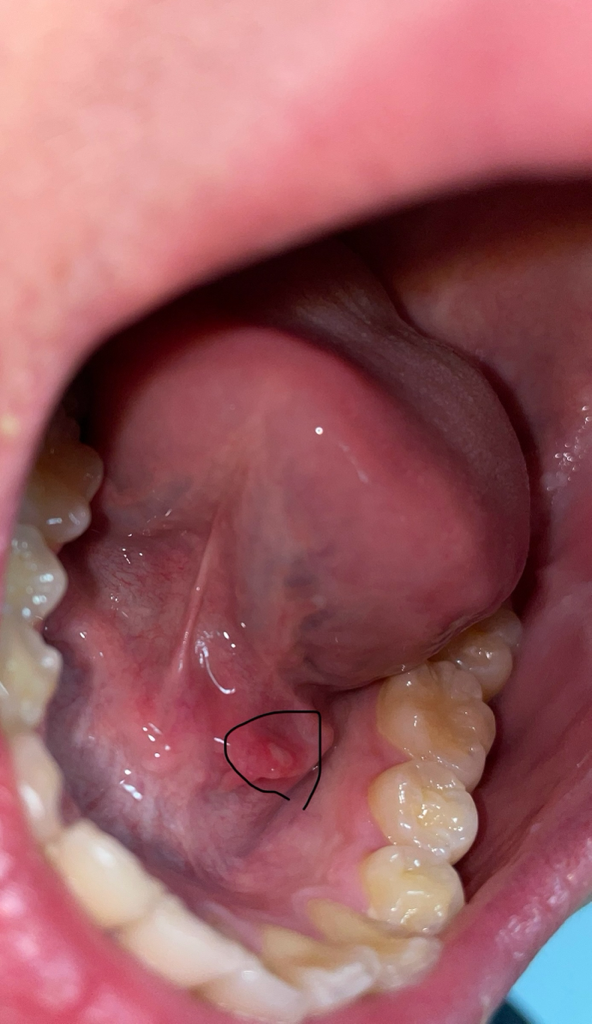

입안 혀아래쪽 수포?염증? 뭐가났어요

저거 생긴진 4일정도됬는데 평상시에 좀 이물감이라던지 밥먹을 때 불편감이 좀 있어서 질문드립니다. 저거 뭔가요? 없애는 방법은 뭐구요..

• 1번 째 사진

• 안녕하세요. 이송재 의사입니다. 사진으로 보았을 때는 구내염으로 생각 됩니다. 궤양성 병변이기 때문에 시간이 지나면 낫지만, 통증이 동반되고 증상이 있다면 가까운 약국에서 알보칠 구매해서 발라 보시기 바랍니다.